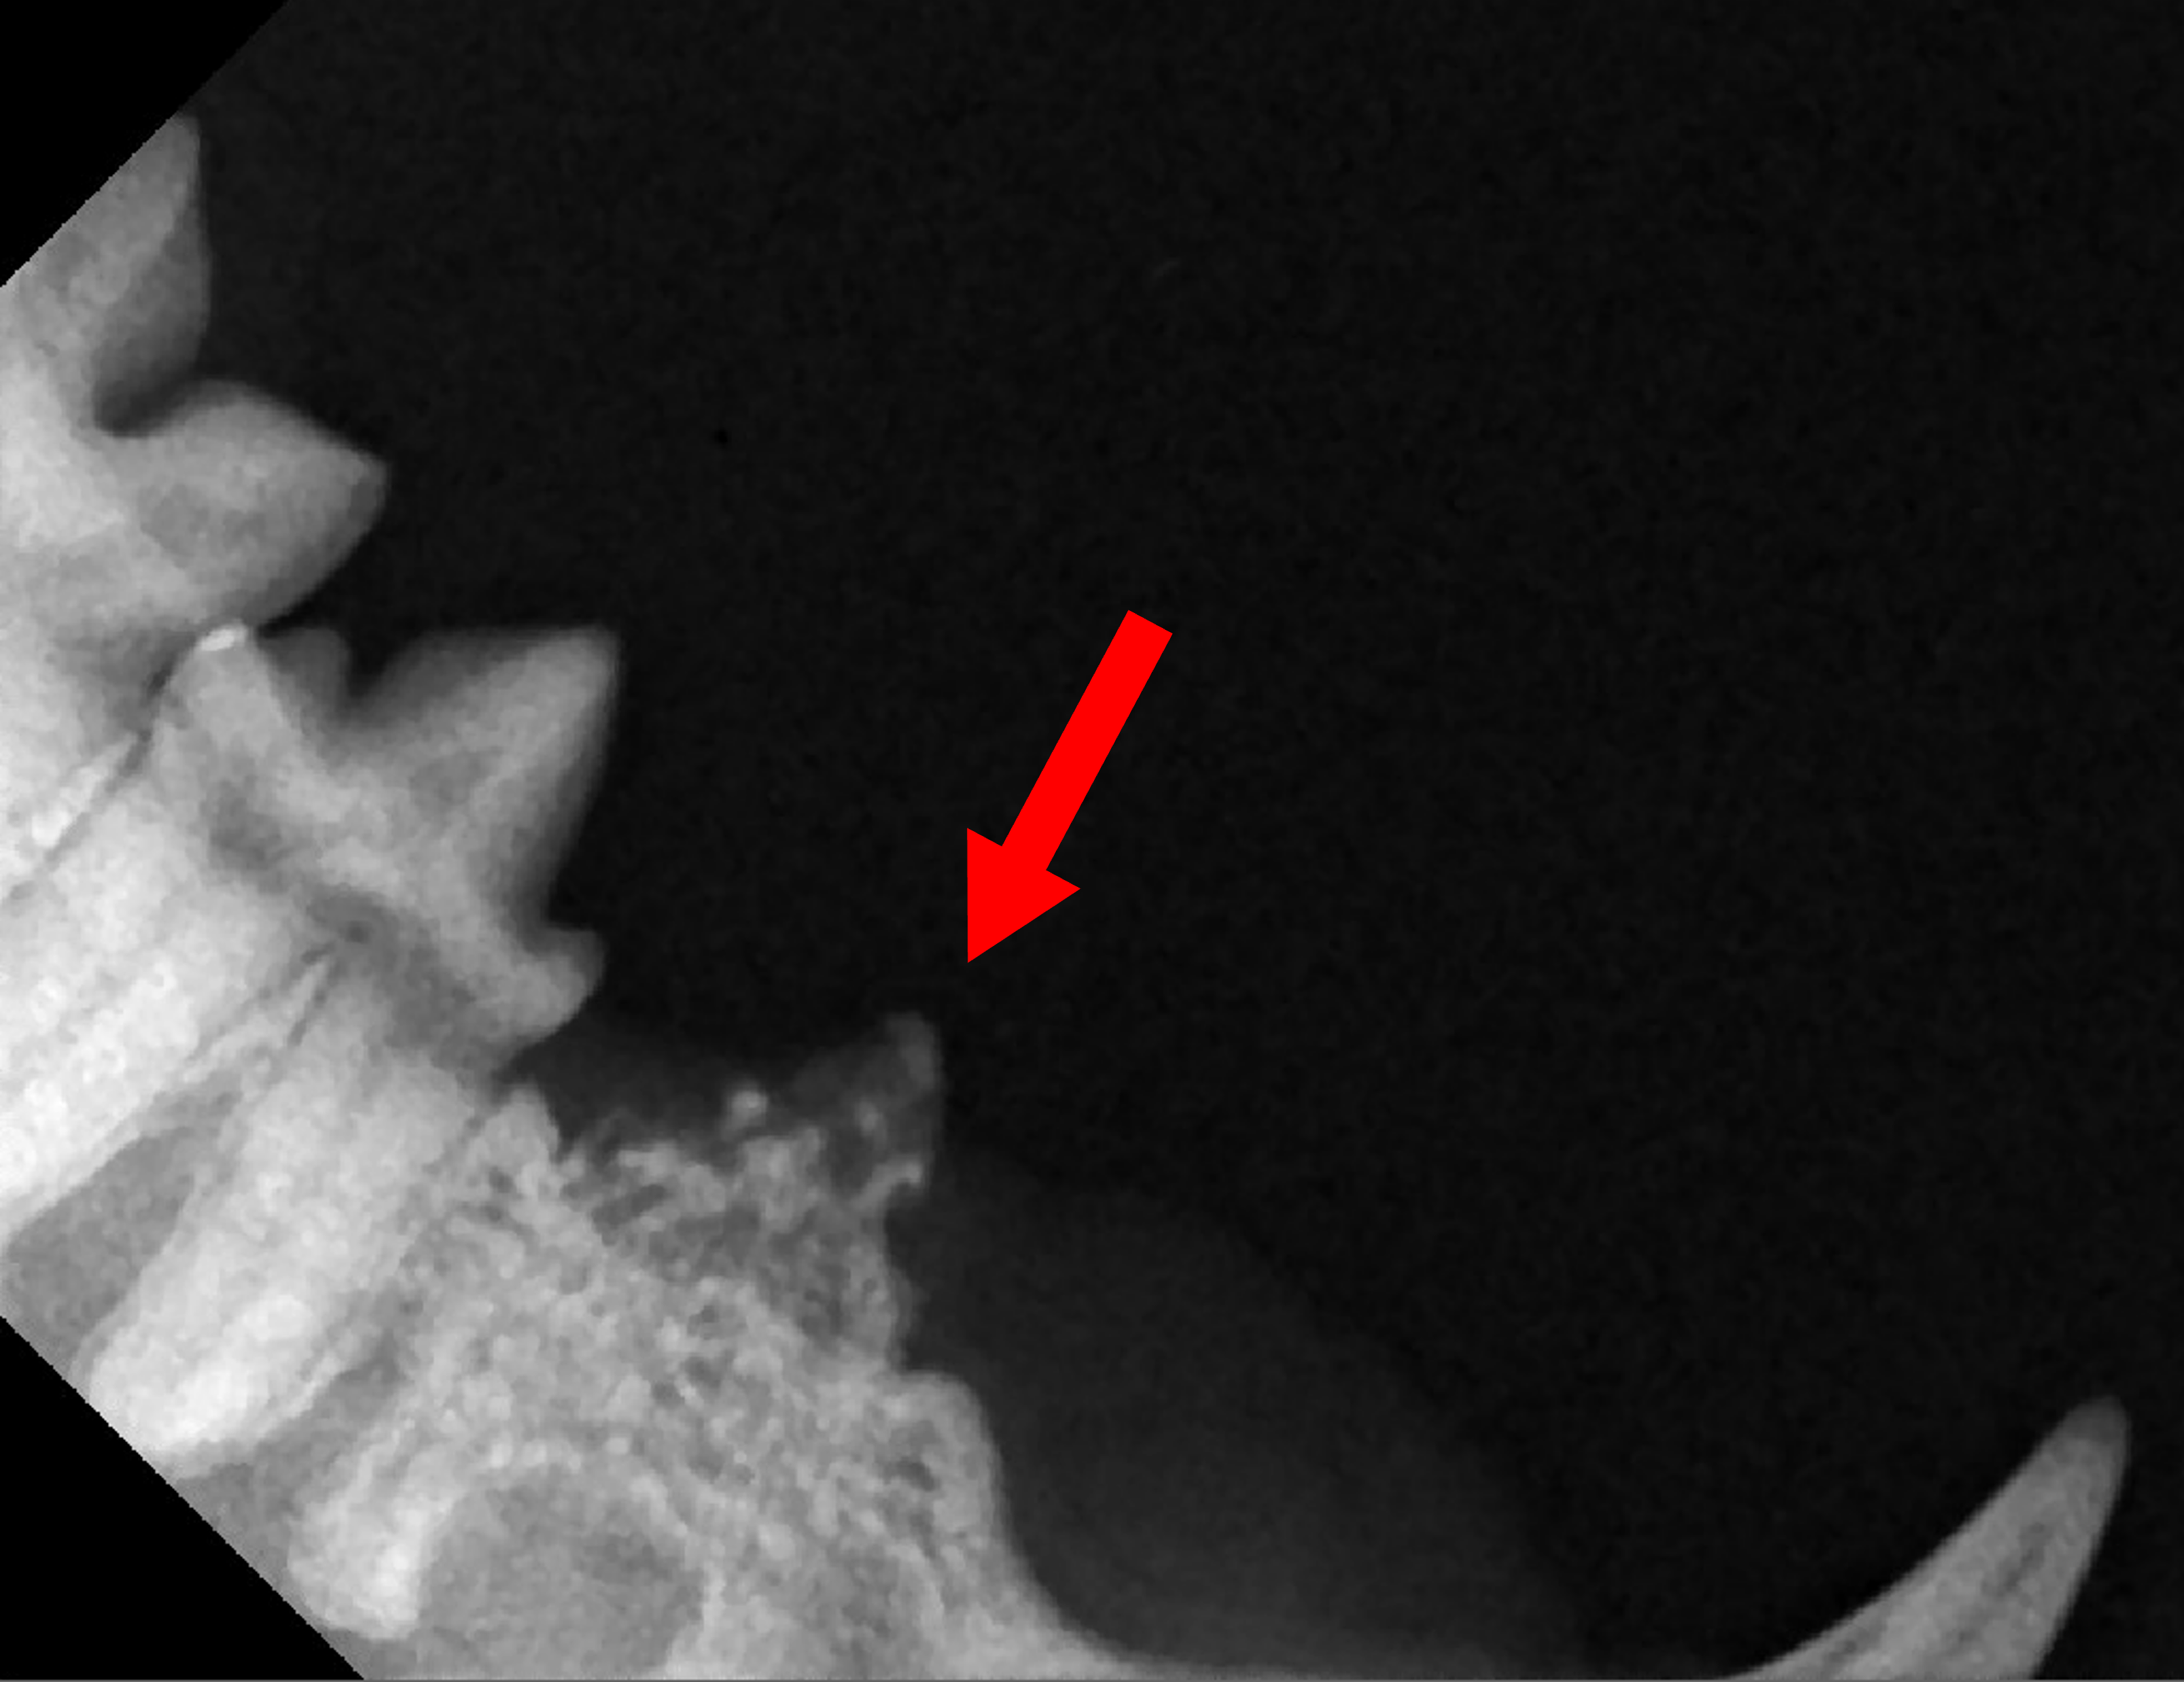

2) 치아 방사선 사진

그 결과 병변이 확인되었습니다. 옆에 있는 정상적인 치아와 비교했을 때, 비정상적인 치주공간 및 흡수성 병변이 확인됩니다.